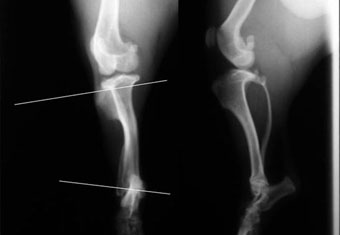

写真上段: 正常な脛骨

膝の関節ラインと足首の関節ラインに白線を引いてあります。これがわずかに外向きに傾くのが正常な状態です。

写真2段目: 手術前の患肢

膝の関節ラインと足首の関節ラインの白線をみると、かなり内側に傾いているのがわかります。膝関節には、不適切な手術で打ち込まれたプレート(白矢印)が写っています。